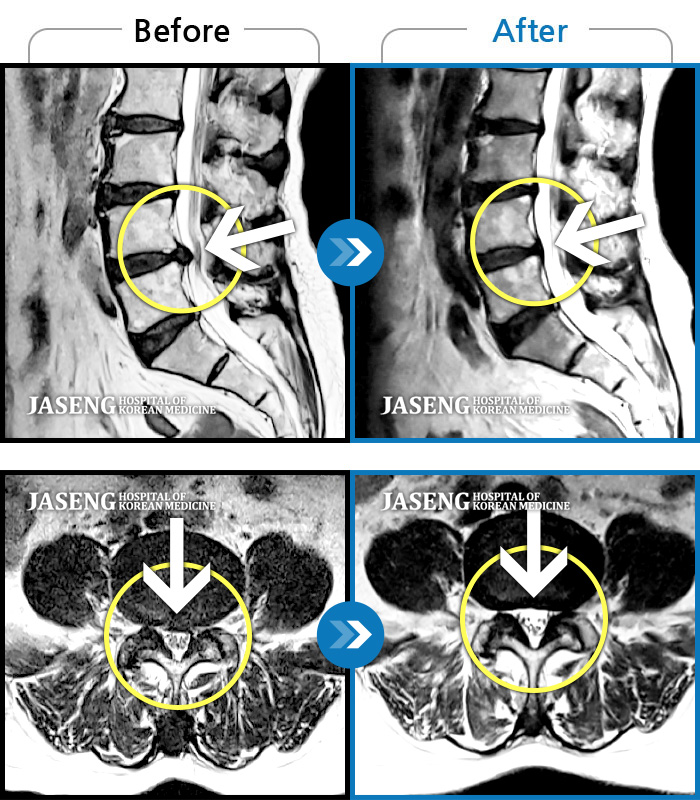

[뱸] 19.11.28~25.05.06